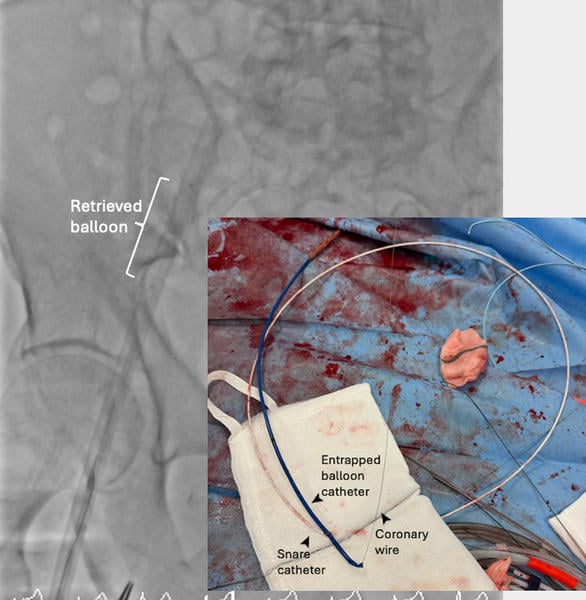

An 81-year-old male patient with symptomatic severe aortic stenosis was admitted for transcatheter aortic valve intervention via right radial and femoral accesses. The native aortic valve was predilated with a 24-mm TrueTM balloon (BD, Franklin Lakes, NJ, USA), delivered via a 12F sheath. The deflated balloon could not be retrieved. Further withdrawal resulted in concertina of the sheath (Figure 1A).

Figure 1. Bailout for aortic valvuloplasty balloon entrapment with schematic illustration of the procedure.

Figure 1A: Failed balloon retrieval.

Physical withdrawal of the unsheathed deflated balloon was considered and briefly attempted but was resisted, and severe damage to the calcified iliac and femoral systems was feared. Snaring of the balloon tip from the right radial access for straightening the system did not help with retrieval (Figure 1B).

Figure 1B: Snaring from right radial access.

Access from the left femoral was considered, but the angulation of the iliac bifurcation was very acute. We therefore cut the balloon and Amplatzer Super StiffTM wire (Boston Scientific, Marlborough, MA, USA) 40 cm from the skin entry point, snared the very tip of the balloon catheter from the right radial artery and internalised the transected balloon system, holding the wire with forceps outside the body for maintaining access, aiming to introduce a larger sheath to help with retrieval (Figure 1C, Moving Image 1).

Figure 1C: ‘Internalisation’ of balloon with a 0.035’ wire running parallel to it (arrowheads).

With a new 0.035’ wire running parallel to the internalised balloon, a 20F sheath was introduced. However, the angle for balloon retrieval remained very unfavorable due to femoral calcification and tortuosity. To straighten the system, A Gaia Next® 2 wire (Asahi Intecc, Aichi, Japan) was used to rewire the central lumen of the transected balloon shaft in a ‘tip-in’ fashion (Figure 1D, Moving image 2).

Figure 1D: ‘Tip-in’ rewiring of central lumen of transected valvuloplasty balloon.

Once this was achieved, internal anchoring with a 2-mm balloon inflated within the wire lumen of the transected valvuloplasty balloon and ipsilateral snaring with a 5-mm Amplatz Goose SnareTM (Medtronic) straightened the system and allowed successful retrieval of the balloon (Figure 1E, Figure 1F, Moving image 3).

Figure 1E: Ipsilateral snaring and 2-mm balloon anchoring in central lumen of transected balloon.

Figure 1F: Successful retrieval of entrapped balloon.